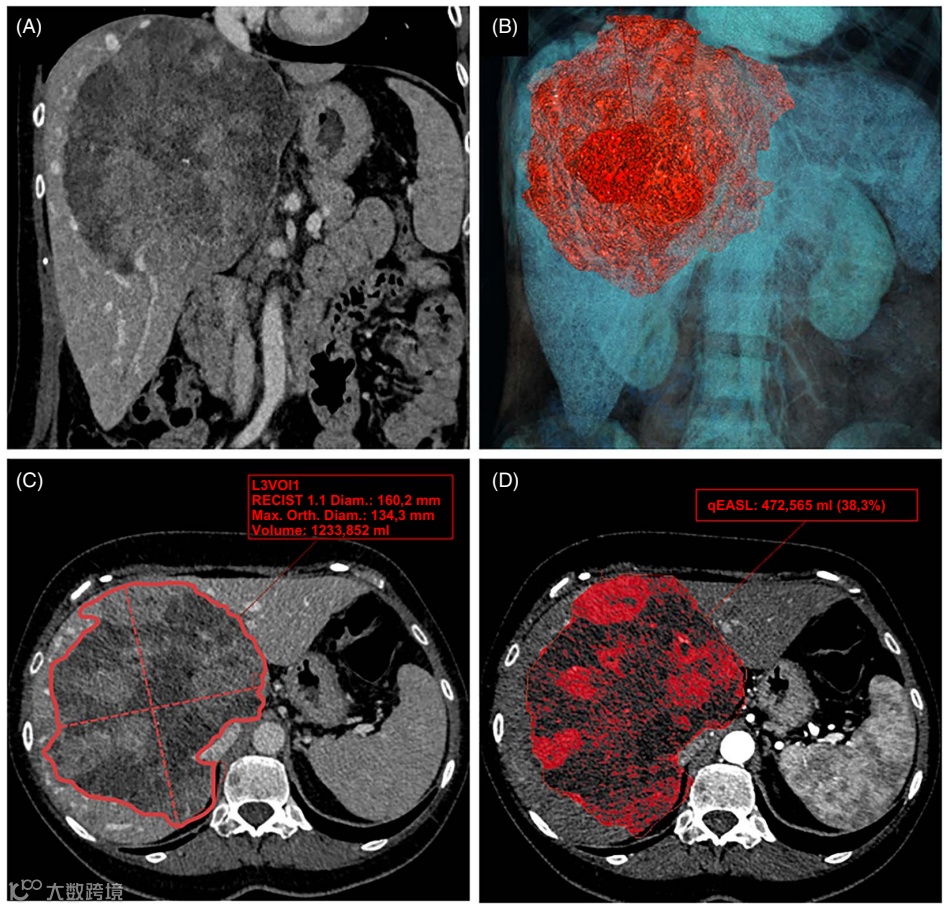

图2展示了3D体积评估技术的应用,相比传统2D测量,它能提供更全面的肿瘤负荷信息。

图2. 一名57岁女性患者,右肝叶患有巨块型HCC。患者接受索拉非尼作为一线治疗,进展后改用瑞戈非尼——两者均为多靶点TKIs。随访2个月的门静脉期对比增强CT图像显示于冠状面(A)和轴状面(C),同时展示了基于分割的肿瘤体积(B)和容积RECIST(vRECIST)评估(B)。动脉期增强病灶体积的量化也显示于图(D),其中红色区域表示由定量EASL(qEASL)标准评估的活性组织。